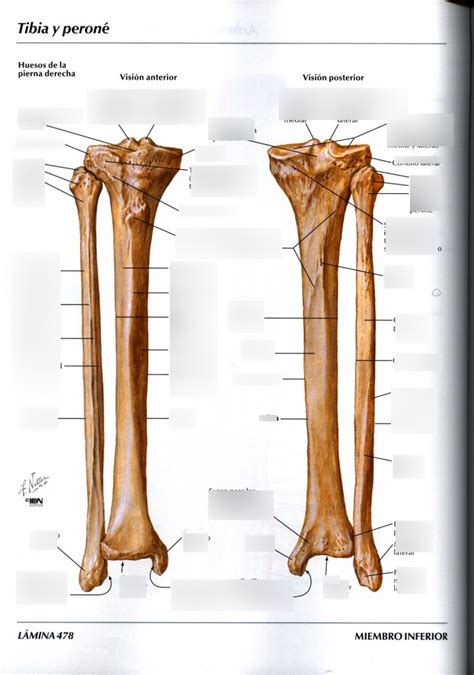

La técnica que más hemos utilizado y que mejores resultados nos ha proporcionado ha sido el colgajo microvascularizado con hueso peroné.

Reconstrucción mandibular con colgajo microvascularizado de peroné

La reconstrucción microquirúrgica con colgajo peroneo fue empleada en 8 pacientes. En 2 optamos por reconstruir utilizando colgajo de músculo temporal (por su localización condilar) y en 2 pacientes se decidió en comité no emplear reconstrucción, dado el avanzado estadiaje de las lesiones.